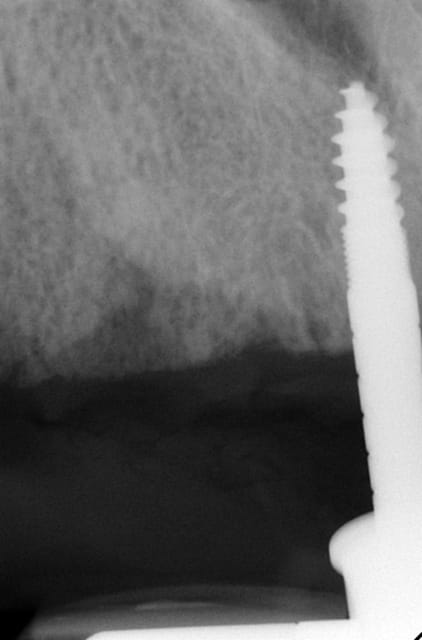

3ème photo: radio d´un patient âgé de 73 ans qui souhaitait avoir des dents fixées.Comme on l´observe il n a plus de place après les foramines mentales.Nous avons donc utilisé juste l´os interforaminal. Nous avons suivi le concept du prof. Nentwig qui consiste à pouvoir ajouter 2 dents dans chaque quadrant dans la mandibule.

Je sais bien que 8 implants auraient suffit cependant 10 ont été posés.Nous voulions remplacer chaque racine avec un implant.

Le patient n a jamais eu de problèmes ( juste avec une hygiène buccale normale, brosse à dents).

Les deux dernières photos montrent le même cas deux ans plus tard.